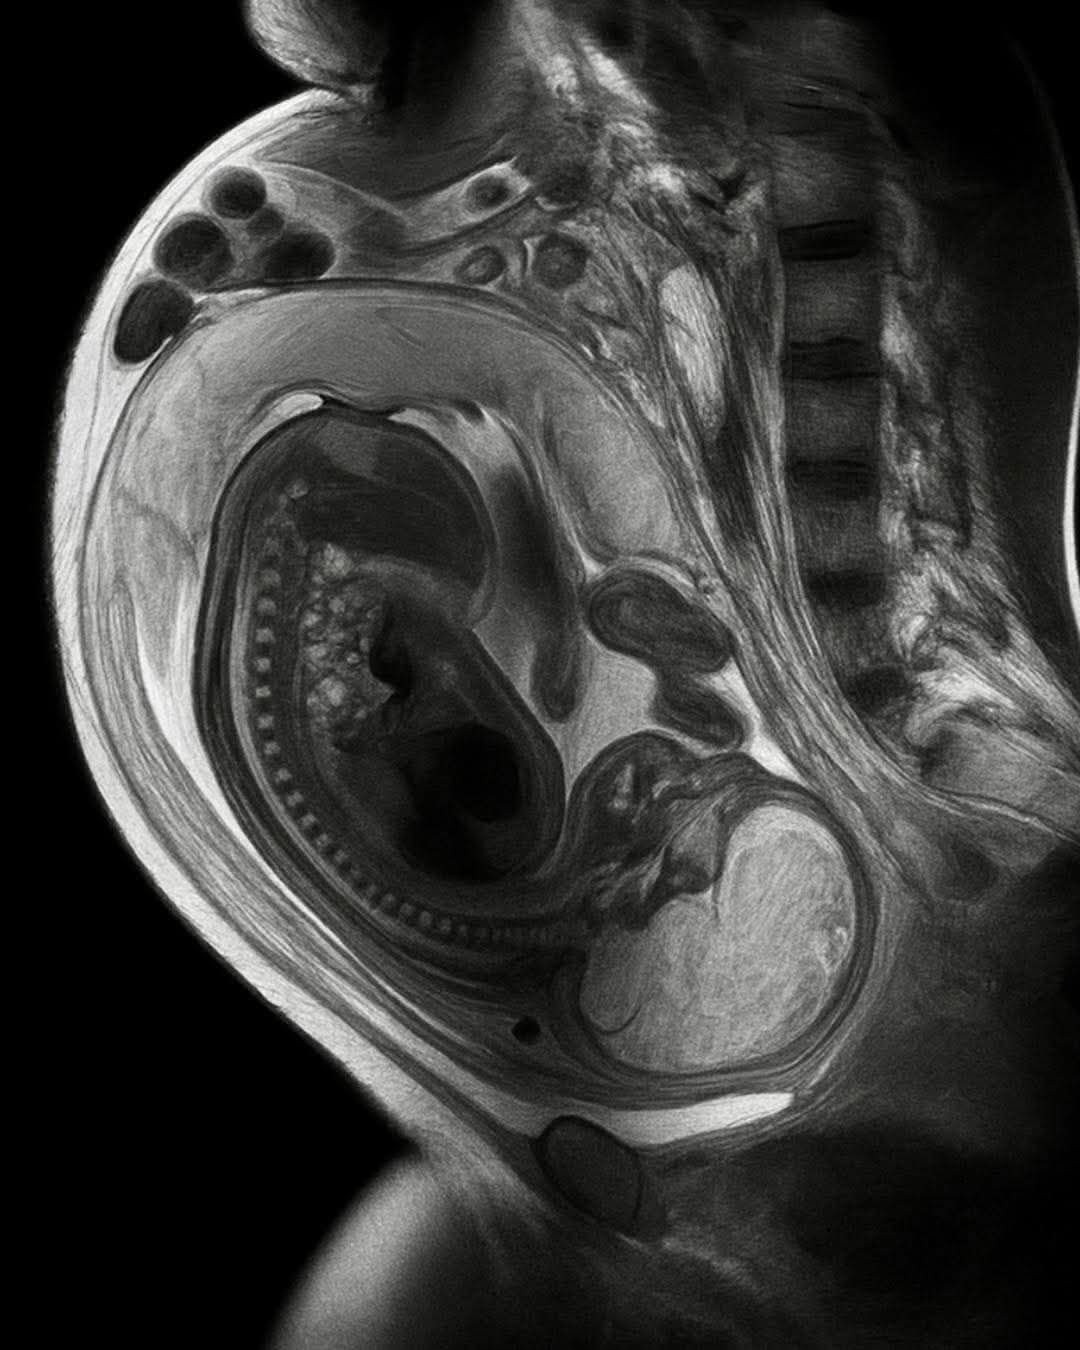

Proses ini bermula sejak dalam kandungan. Plasenta tidak hanya berperan sebagai jalur distribusi nutrisi, tetapi juga menjadi medium pertukaran sel. Sel-sel janin dapat masuk ke tubuh ibu dan menetap di berbagai organ penting seperti jantung, hati, paru-paru, hingga otak. Yang mengejutkan, sel-sel ini mampu bertahan selama puluhan tahun setelah kehamilan berakhir.

Pertukaran sel terjadi secara dua arah. Tubuh ibu juga mengirimkan sel ke dalam tubuh janin, yang kemudian menetap di berbagai jaringan anak, termasuk sistem imun dan otak. Diperkirakan, satu dari setiap satu juta sel dalam tubuh manusia berasal dari ibu. Dengan total sekitar 30 triliun sel dalam tubuh manusia, ini berarti jutaan sel ibu hidup dan berfungsi dalam tubuh anak sepanjang hidupnya.